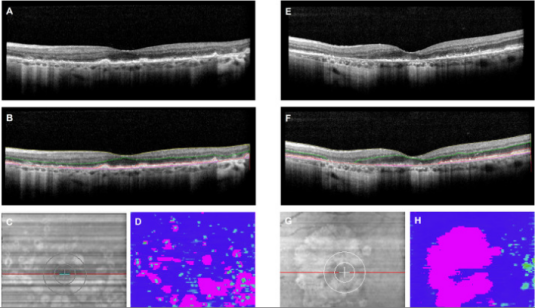

GATHER1 examined the efficacy and safety of avacincaptad pegol (ACP) for GA treatment. A post hoc analysis was performed to identify correlations between FAF- and OCT-based measurements of GA. GA area was measured on blue-light FAF images using semiautomatic segmentation software with support from OCT and near-infrared imaging. Machine-learning enhanced, multilayer segmentation of OCT scans were reviewed by human readers, and segmentation errors were corrected as needed. GA area was defined as total RPE loss on cross-sectional B scans. Time points included Months 0, 6, 12, and 18. Additionally, OCT-based GA-area changes between ACP and sham were analyzed.

GATHER1研究评估了avacincaptad pegol(ACP)治疗GA的有效性和安全性。进行事后分析以确定基于FAF与OCT的GA测量值相关性。在蓝光FAF图像上采用半自动分割软件测量GA面积,并结合OCT及近红外成像进行辅助确认。人工阅片者对经机器学习增强的多层OCT扫描分割结果进行审查,并在必要时对分割误差进行修正。GA面积定义为横断面B扫描中的总RPE缺失面积。评估时间点包括第0、6、12和18个月。此外,还分析了ACP组与假手术组之间基于OCT的GA面积变化。

There was a strong correlation (r = 0.93) between FAF and OCT GA area measurements that persisted through 18 months. Mean (SD) differences between OCT and FAF GA measurements were negligible: 0.11 mm2 (1.42) at Month 0, 0.03 mm2 (1.62) at Month 6, -0.17 mm2 (1.81) at Month 12, and -0.07 mm2 (1.78) at Month 18. OCT assessments of GA growth revealed a 30% and 27% reduction at Months 12 and 18, respectively, between ACP and sham, replicating FAF measurements from GATHER1.

FAF与OCT测得的GA面积在18个月内显示出高度相关性(r = 0.93)。OCT与FAF测得的GA均值(SD)差异可忽略不计:第0月为0.11 mm2(1.42),第6月为0.03 mm2(1.62),第12月为-0.17 mm2(1.81),第18月为-0.07 mm2(1.78)。OCT评估显示,ACP组与假手术组在第12个月和第18个月的GA增长率分别降低30%和27%,与GATHER1研究中FAF测量结果一致。

The strong correlation between blue FAF and OCT measurements of GA area supports OCT as a reliable method to measure GA lesion area in clinical trials.

蓝光FAF与OCT测得的GA面积存在高度相关性,证实了OCT是临床试验中测量GA病灶面积的可靠方法。